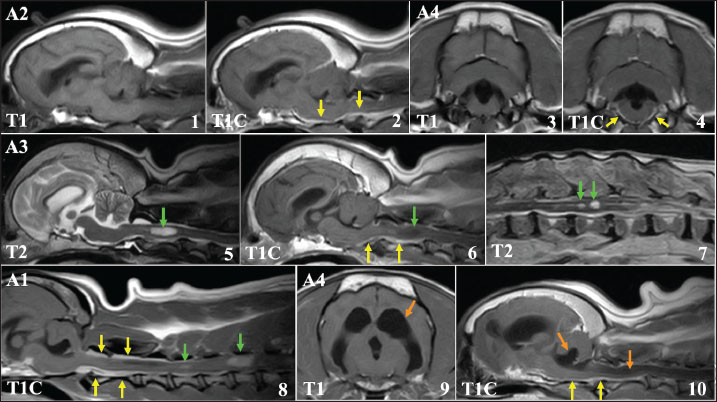

The MRI features of these recurring cases (A1–A4) are shown in Fig. 4. In all 4 cases, MRI showed that the primary tumor tissues had almost completely disappeared. However, in the contrast study, sagittal T1-weighted images of these 4 cases showed clear enhancement in the leptomeningeal region, which was most evident in the area spanning the ventral side of the brainstem to the cervical spinal cord (Fig.4,1-4). In addition to these leptomeningeal enhancements, two cases (A1 and A3) had space-occupying lesions in the cervical and/or thoracolumbar spinal cord along the central canal of the spinal cord (Fig.4,5-8). The signal intensities of both lesions were slightly low in T1-weighted images, and slightly high in T1-weighted and T2-weighted images, respectively. The spinal lesion showed only minor enhancement in one patient, but there was clear enhancement in the other. Furthermore, in case A3, multiple mass lesions were found in the thoracolumbar spinal cord (Figs. 4 and 7). Significant obstructive hydrocephalus was observed in one case (A4, Fig.4, 9-10). These findings are highly similar to those showing CSF drop metastasis, which was recently reported in dogs (Vigeral et al., 2018; Bentley et al., 2021).

Fig. 4. MRI findings of FB cases in which clinical symptoms recurred after radiotherapy (cases A1–A4, T1: T1-weighted image, T2: T2-weighted image, T1C: T1-weighted image with contrast medium). Upper lane (1–4): A clear enhancement was observed in the meninges around the brainstem (yellow arrows). Middle lane (5–7): Spinal lesions observed at clinical recurrence (green arrows). The lesion located in the central cervical spinal cord of case A3 showing high-signal intensity on T2-weighted image (5) showed no contrast enhancement (6, green arrow), whereas the leptomeningeal region showed clear enhancement (6, yellow arrows). Multiple lesions were also observed in the thoracolumbar spinal cord in this case (7). Lower lane (8–10): Cervical spinal lesions in patient A1. Unlike case A3, these lesions showed clear enhancement, similar to that of the leptomeningeal region (8, green arrows). In case A4, severe obstructive hydrocephalus was observed, with dilated lateral (9) and fourth (10) ventricles (orange arrows).